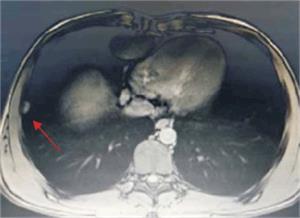

Hepatomegalia difusa de densidad heterogénea a expensas de múltiples lesiones sólidas, con realce en tiempo arterial; la de mayor tamaño ocupa la mayor parte del lóbulo izquierdo de 161 por 70 por 100 mm, de contornos irregulares (figura 1). Se observa en el segmento VI lesión nodular de 9 mm y en el segmento VII de 20 mm.

Adenomegalias y conglomerados a nivel intercavoaórticos de 43 por 42 mm, a la altura del hilio renal izquierdo, y lateoraórtico de 35 por 30 mm. Tórax: imagen nodular pleural derecha de 15 mm.